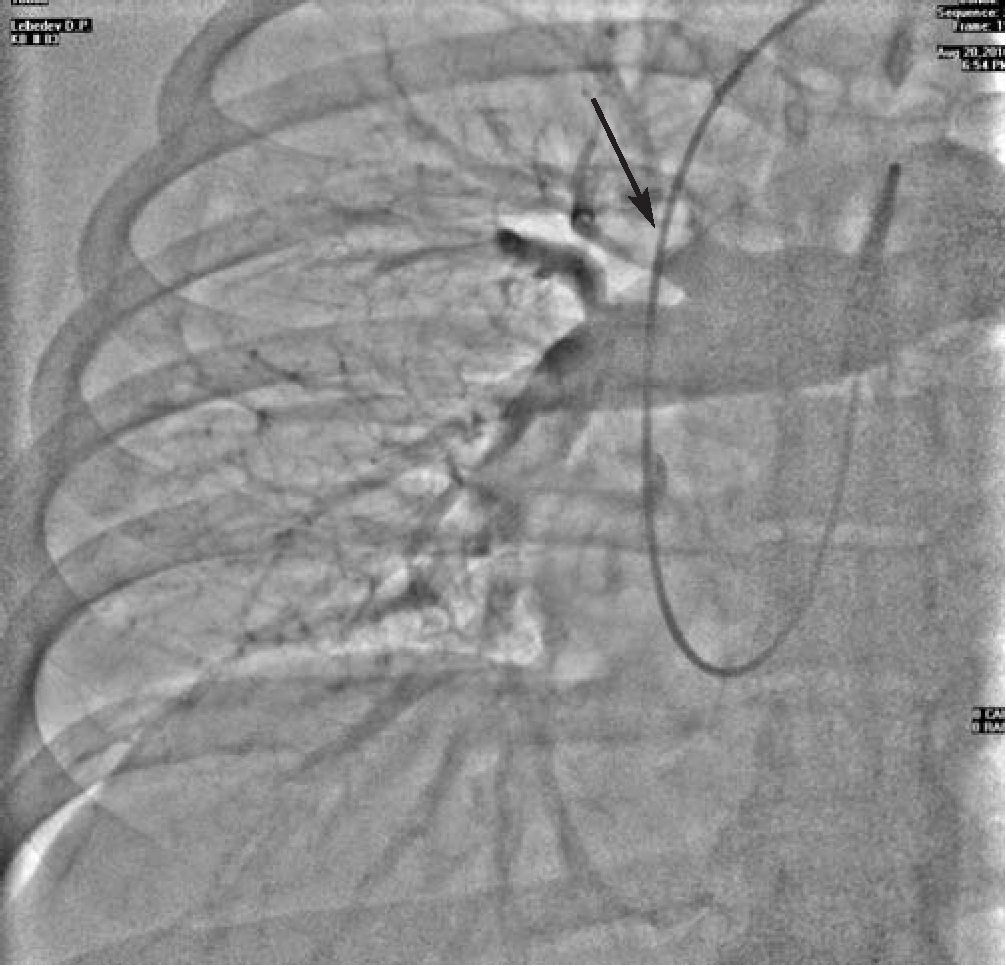

При проведении ангиопульмонографии выявлен округлый внутрипросветный дефект контрастирования размерами 2,0x1,5 см верхнедолевой ветви правой легочной артерии - ангиографические признаки субмассивной ТЭЛА (см рис.).

Рис. Ангиограмма правой главной ветви легочной артерии. Стрелка указывает на дефект наполнения.

Тем не менее, «золотым стандартом» в диагностике ТЭЛА остается ангиопульмонография, чувствительность и специфичность которой приближаются к 100%. Больной Л. было проведено ангиографическое исследование, которое позволило подтвердить диагноз ТЭЛА и выявить локализацию тромба.